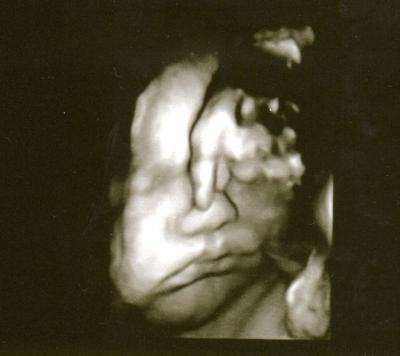

Mein kleiner Dicker ;)

Hier mal wieder ein Bild vom Spatz

Ha, ha der ist ja süss will er gerade abtauchen !!! Zum Knuddeln sieht er aus und mega geniales Bild echt !!!!

Wir haben eher gedacht er will uns damit sagen ihr stinkt mir...ich will endlich wieder meine Ruhe ;)

och wie süss so ein schönes Bild und so ein hübscher Kleiner der hat ja schon ein richtiges Doppelkinn ist er schon so speckig wie weit bist du denn? lg Kristin

Da war ich bei 36+2 SSW, das arme Kind ist so dick weil meine Ärztin die SS- Diabetis nicht festgestellt hat. An dem Tag haben sie ihn auf 3455 g geschätzt :(

Oh man der ist ja echt süß. Kaum vorstellbar, dass da so ein richtig kleines fertiges Baby im Bauch ist. Ich hoffe es geht dem Kleinen trotz SS Diabetes gut. Mein Sohn hatte bei der Geburt über 4500g und ich fand ihn gar nicht so groß und dick (naja außer wenn er neben 3000g Babys lag)... Jetzt ist er übrigens 4 Jahre alt und eher schmächtig für sein Alter.